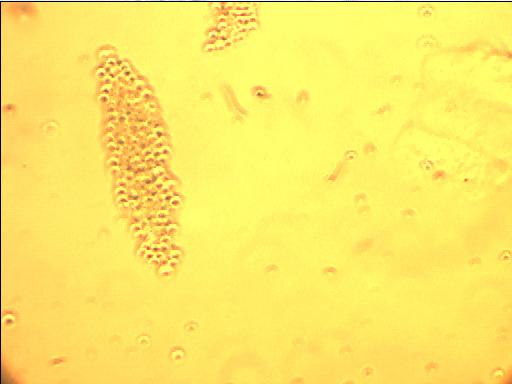

ϸ°û±§ÍźÍϸ°ûȾ¾úÔõÃ´Çø±ð°¡ ÒÑÓÐ1È˲ÎÓë